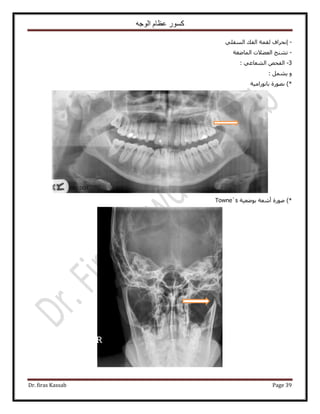

٢‫حُ٘ؼخػ‬ ٚ٤‫حُظ٘و‬:

‫ح٩ٗخٍس‬ ٖٓ ‫٫ري‬‫ح‬ ٞ‫ُزؼ‬‫كظخص‬ ٬ُٔ: ‫ٗؼخػ٤خ‬ ‫حُٞؿٜ٤ش‬ ‫ح٧ً٣خص‬ ٚ٤‫ط٘و‬ ٚ٤‫طٞؿ‬ ٝ ْٜ‫ُل‬

‫أ‬‫وال‬:

*٩‫ح‬ َ‫هز‬ ‫٣ـذ‬، ‫حُ٘ؼخػ٤ش‬ ‫حُٔلَىحص‬ ٠ِ‫ػ‬ ‫١٬ع‬‫أ‬٢٤‫ٗل‬ ٕ‫ػِٔخ‬٤‫حُظَ٘٣ل‬ ‫رخُٔ٘خ١ن‬ٝ ‫ٗؼخػ٤خ‬ ‫حُٔيٍٝٓش‬ ‫ش‬ٌَُٔ‫ح‬ ١ٞ‫روط‬‫أ‬ٝ

‫ٓ٘خ١ن‬‫حُولل٤ش‬ ‫حُٞؿٜ٤ش‬ ‫حُ٠ؼق‬.

*ُٔ‫ح‬ ٠‫حُطزو‬ َ٣ٜٞ‫حُظ‬ ‫ٗطزن‬ ‫هخٛش‬ ٚ‫حُٞؿ‬ ًٍٞٔ ٠َٟٓ ٢‫ك‬ٝ ٍٟٞ‫ل‬‫ٓلٍٞ٣ش‬ ‫ٓوخ١غ‬ ٖ‫ػ‬ ‫ػزخٍس‬ ٞٛ‫أ‬ٝ ‫١زو٤ش‬ ٝ‫ا‬‫ؿزٜ٤ش‬ ‫ًِ٤ِ٤ش‬

ٛٝ٢‫ر٤ٜ٘خ‬ َٜ‫٣ل‬ ‫حَُٝط٤٘٤ش‬ ‫حُٔوخ١غ‬3–5ٝ ْٓ‫ٍرٔخ‬‫أ‬ٝ ، َ‫ه‬٣٧‫ح‬ ُِٕٞ‫ح‬ ٍ‫ي‬ٝ ، ‫حُؼظ٤ٔش‬ ‫حُٔخىس‬ ٠ِ‫ػ‬ ٞ٤‫ر‬‫ح‬٧‫ح‬ ُِٕٞ٠ِ‫ػ‬ ‫ٓٞى‬

‫حُ٘لٔ٤ش‬ ‫حُٔخىس‬‫أ‬‫حَُهٞس‬ ‫حُ٘ٔؾ‬ ٝ.

‫ًؼخكخ‬ ‫٣َ٣٘خ‬ ‫ًٔخ‬ِٚ‫ريحه‬ ‫حُٜٞحء‬ ‫ٓغ‬ ٠ٌ‫حُل‬ ‫حُـ٤ذ‬ ‫ص‬‫أ‬‫ح‬ َ‫ريحه‬ ٝ‫ُلـخؽ‬‫أ‬ٍٞٓ‫ٗخ‬ ‫ٗظ٤ـش‬ ‫حُولق‬ ٌٖٝٝٔ٣‫ا‬‫حُٔوخ١غ‬ ٌٙٛ ٍ‫ٍٓخ‬‫ا‬٠ُ

ٝ ‫ُ٘خ‬ ‫ُ٤ـٜٔٔخ‬ َ‫حٌُٔز٤ٞط‬ٝ ‫ٓـٔٔخ‬ ‫ٓ٘ظَح‬ ‫٣ؼط٤٘خ‬ٝ ‫حُـَحكش‬ َ‫هز‬ ٚ‫حُٞؿ‬ َ‫ط٘خظ‬ ‫ُ٘خ‬ ْ٤‫٣و‬ ‫ٌٛح‬‫حُـَحك٤ش‬ ‫رؼي‬ ٚ‫ٟٝؼ‬ٝ‫أ‬ٟ‫ٓٔخإ‬ ْٛ

ُ‫ح‬ ‫ٌٛح‬٧‫ح‬ ٠‫حُؼ٬ػ‬ ٍٟٞ‫حُٔل‬ ٠‫حُطزو‬ َ٣ٜٞ‫ظ‬‫رؼ‬‫ٌُٔ٤ش‬ ٞ٣َُٔ‫ح‬ َٝ‫طؼ‬ ٢ٛ ْٔ‫حُٔـ‬ ‫خى‬‫أ‬‫ح٫ٗؼش‬ ٖٓ َ‫ًز‬.